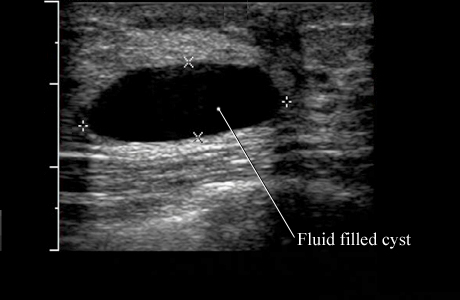

Ultrasound of a Simple Breast CystCourtesy

of Intermountain Medical Imaging, Boise, Idaho. This

ultrasound picture shows a simple cyst with normal breast tissue around it.

Because this type of cyst usually does not have any tissue or other particles

in it, your doctor knows that it is fluid-filled and can be drained if